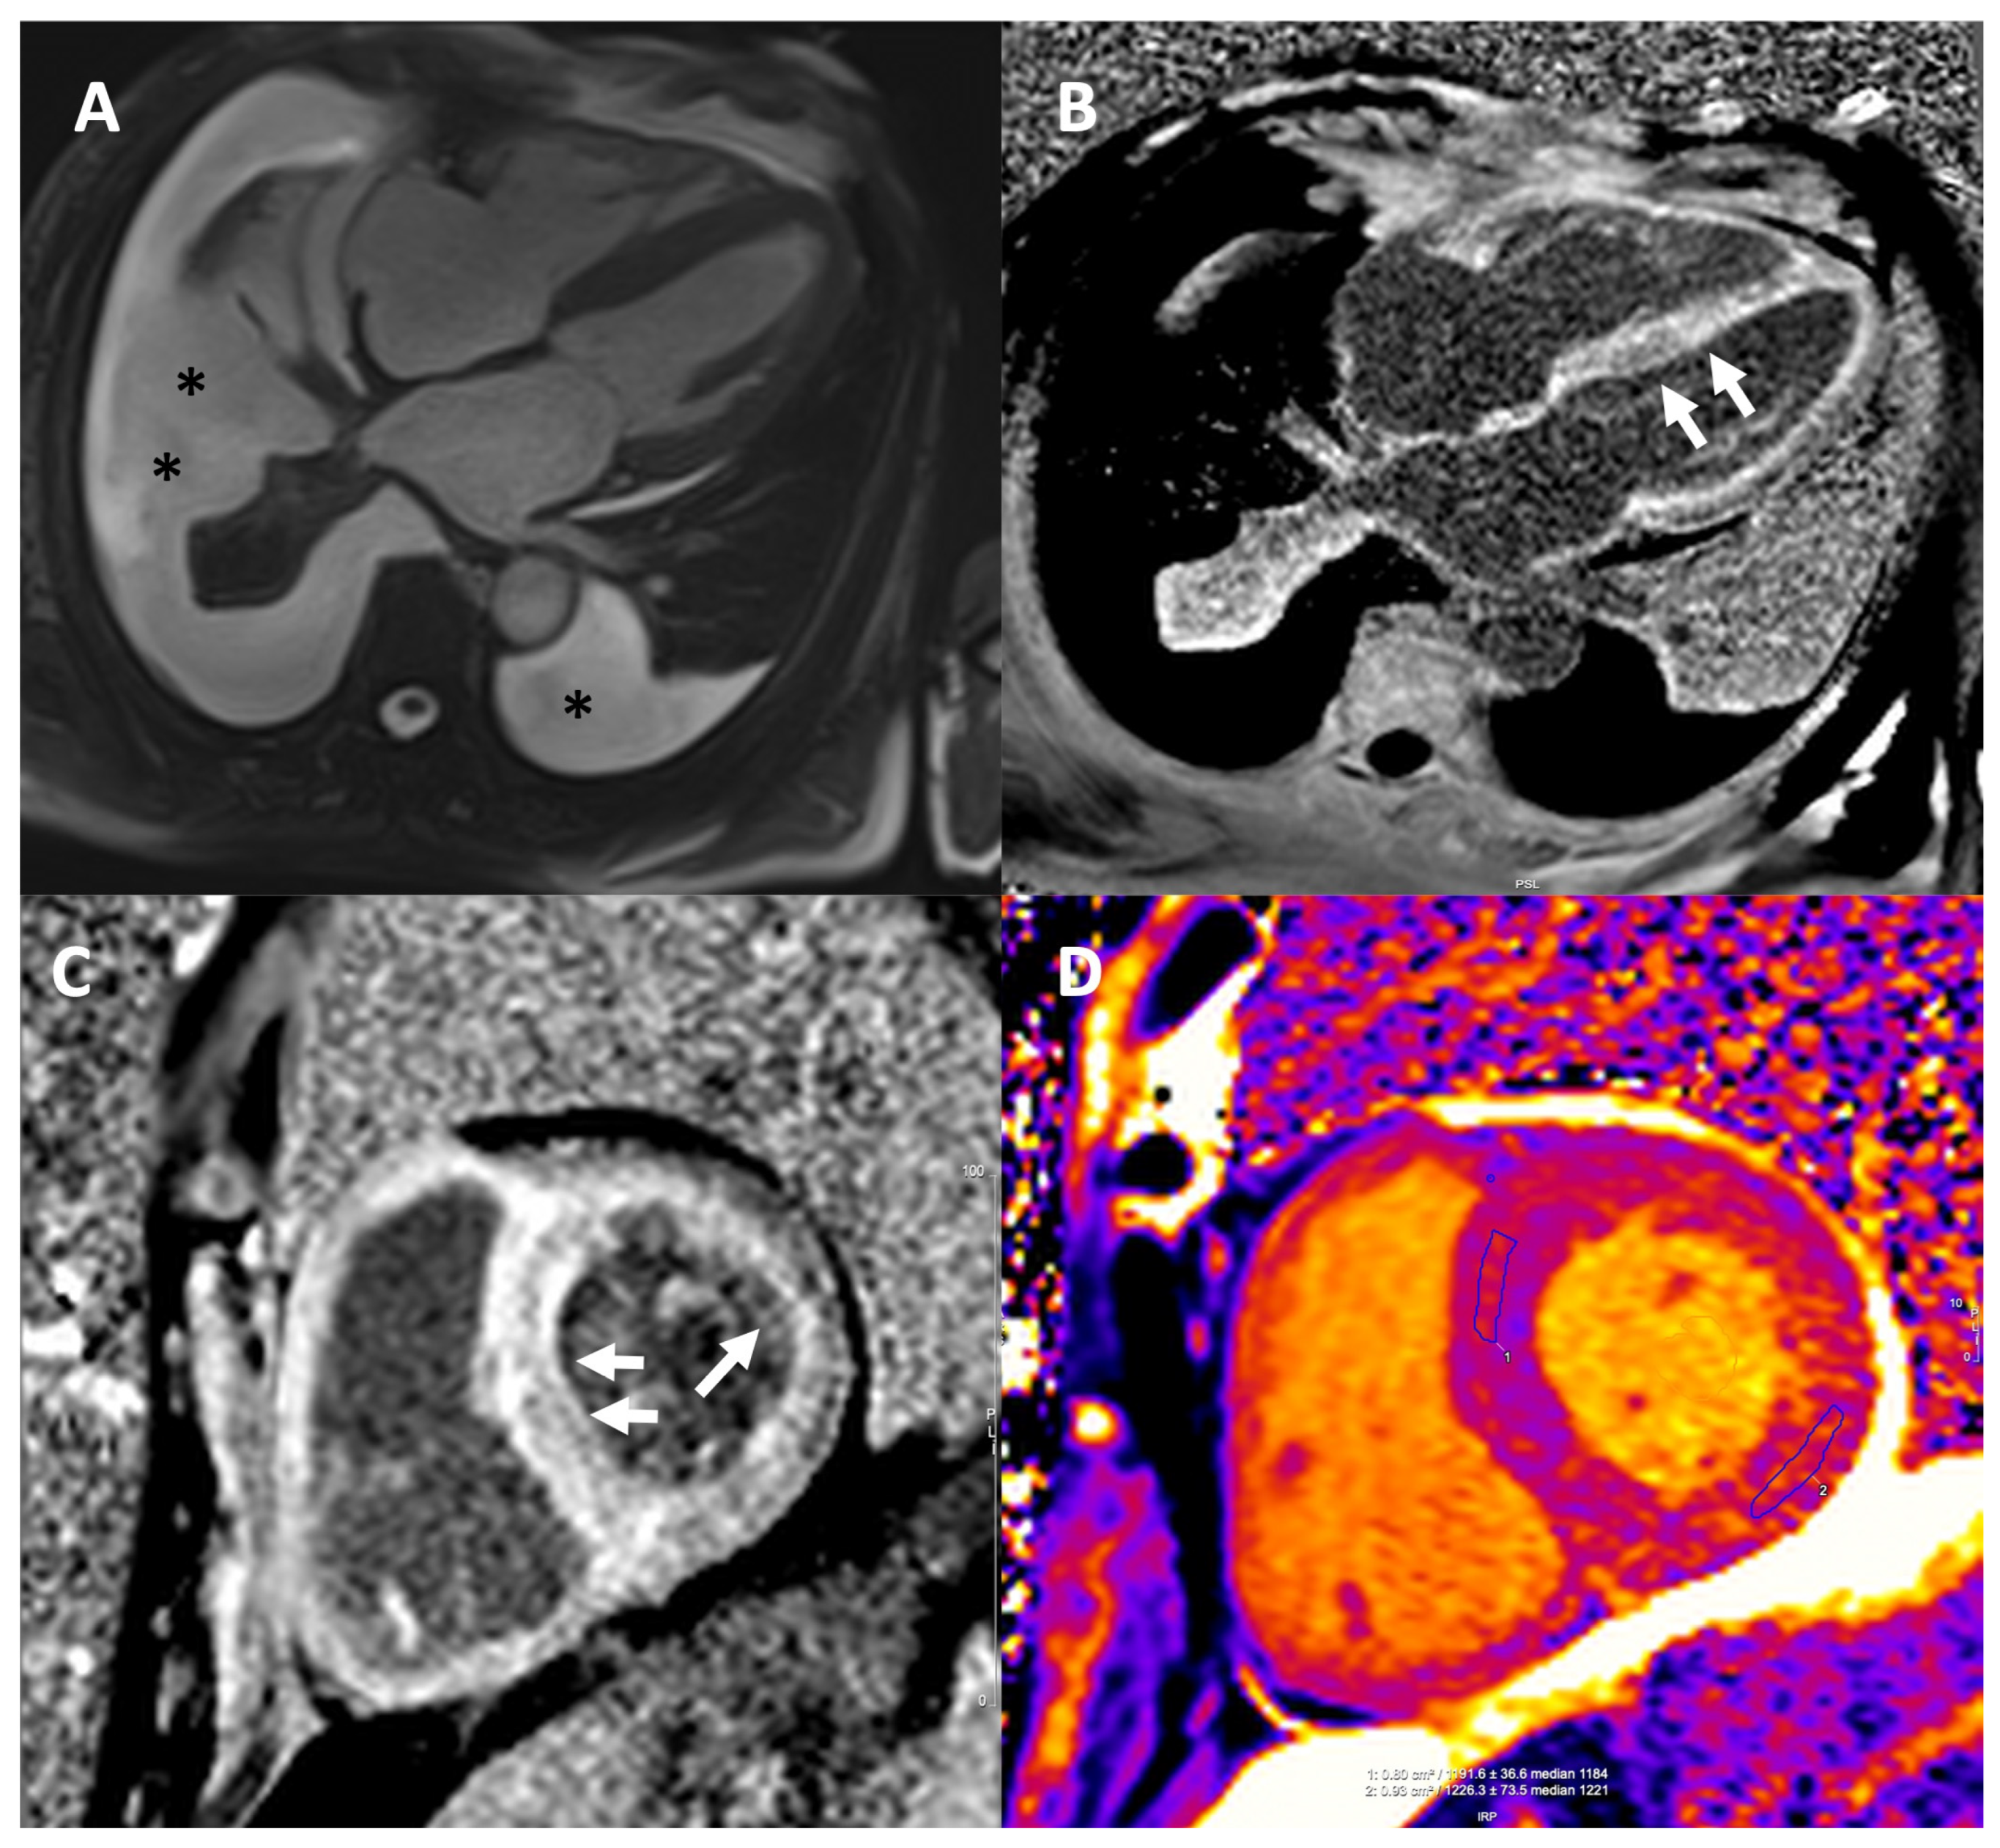

7. Cardiac Magnetic Resonance

7.1. CMR for Diagnosis

7.2. CMR for Prognosis

7.3. CMR for Monitoring the Response to Treatment

- Burrage, M.K.; Ferreira, V.M. Cardiovascular Magnetic Resonance for the Differentiation of Left Ventricular Hypertrophy. Curr. Heart Fail. Rep. 2020, 17, 192–204. [Google Scholar] [CrossRef]

- Licordari, R.; Trimarchi, G.; Teresi, L.; Restelli, D.; Lofrumento, F.; Perna, A.; Campisi, M.; de Gregorio, C.; Grimaldi, P.; Calabrò, D.; et al. Cardiac Magnetic Resonance in HCM Phenocopies: From Diagnosis to Risk Stratification and Therapeutic Management. J. Clin. Med. 2023, 12, 3481. [Google Scholar] [CrossRef]

- Maceira, A.M.; Joshi, J.; Prasad, S.K.; Moon, J.C.; Perugini, E.; Harding, I.; Sheppard, M.N.; Poole-Wilson, P.A.; Hawkins, P.N.; Pennell, D.J. Cardiovascular Magnetic Resonance in Cardiac Amyloidosis. Circulation 2005, 111, 186–193. [Google Scholar] [CrossRef]

- Karamitsos, T.D.; Piechnik, S.K.; Banypersad, S.M.; Fontana, M.; Ntusi, N.B.; Ferreira, V.M.; Whelan, C.J.; Myerson, S.G.; Robson, M.D.; Hawkins, P.N.; et al. Noncontrast T1 Mapping for the Diagnosis of Cardiac Amyloidosis. JACC Cardiovasc. Imaging 2013, 6, 488–497. [Google Scholar] [CrossRef]

- Baggiano, A.; Boldrini, M.; Martinez-Naharro, A.; Kotecha, T.; Petrie, A.; Rezk, T.; Gritti, M.; Quarta, C.; Knight, D.S.; Wechalekar, A.D.; et al. Noncontrast Magnetic Resonance for the Diagnosis of Cardiac Amyloidosis. JACC Cardiovasc. Imaging 2020, 13, 69–80. [Google Scholar] [CrossRef]

- Brooks, J.; Kramer, C.M.; Salerno, M. Markedly Increased Volume of Distribution of Gadolinium in Cardiac Amyloidosis Demonstrated by T1 Mapping. J. Magn. Reason. Imaging 2013, 38, 1591–1595. [Google Scholar] [CrossRef]

- Martinez-Naharro, A.; Kotecha, T.; Norrington, K.; Boldrini, M.; Rezk, T.; Quarta, C.; Treibel, T.A.; Whelan, C.J.; Knight, D.S.; Kellman, P.; et al. Native T1 and Extracellular Volume in Transthyretin Amyloidosis. JACC Cardiovasc. Imaging 2019, 12, 810–819. [Google Scholar] [CrossRef]

- Pan, J.A.; Kerwin, M.J.; Salerno, M. Native T1 Mapping, Extracellular Volume Mapping, and Late Gadolinium Enhancement in Cardiac Amyloidosis: A Meta-Analysis. JACC Cardiovasc. Imaging 2020, 13, 1299–1310. [Google Scholar] [CrossRef]

- Martinez-Naharro, A.; Abdel-Gadir, A.; Treibel, T.A.; Zumbo, G.; Knight, D.S.; Rosmini, S.; Lane, T.; Mahmood, S.; Sachchithanantham, S.; Whelan, C.J.; et al. CMR-Verified Regression of Cardiac AL Amyloid After Chemotherapy. JACC Cardiovasc. Imaging 2018, 11, 152–154. [Google Scholar] [CrossRef] [PubMed]

- Fontana, M.; Pica, S.; Reant, P.; Abdel-Gadir, A.; Treibel, T.A.; Banypersad, S.M.; Maestrini, V.; Barcella, W.; Rosmini, S.; Bulluck, H.; et al. Prognostic Value of Late Gadolinium Enhancement Cardiovascular Magnetic Resonance in Cardiac Amyloidosis. Circulation 2015, 132, 1570–1579. [Google Scholar] [CrossRef] [PubMed]

- Kato, S.; Azuma, M.; Horita, N.; Utsunomiya, D. Monitoring the Efficacy of Tafamidis in ATTR Cardiac Amyloidosis by MRI-ECV: A Systematic Review and Meta-Analysis. Tomography 2024, 10, 1303–1311. [Google Scholar] [CrossRef]